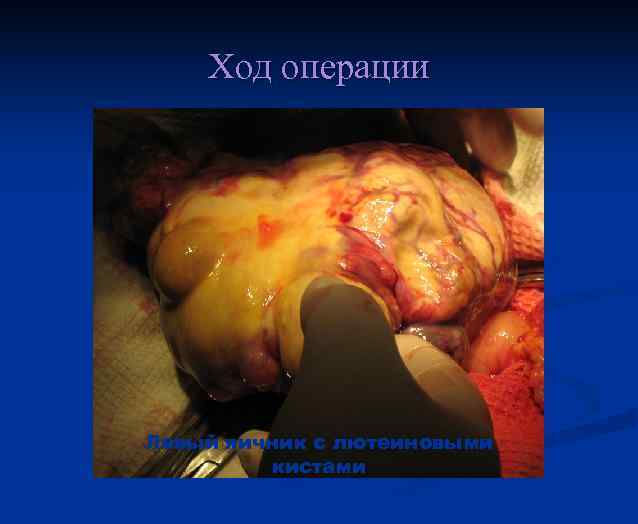

Клиника n n Нарушение менструальной функции(у 53, 7 % позднее менархе). Несоответствие размеров матки предполагаемому сроку беременности (у 50— 86 % больных). Образование лютеиновых кист яичников (в 50 % случаев). Появляются в течение первых 2 нед. Наличие их служит неблагоприятным прогностическим признаком. Обратное развитие лютеиновых кист отмечается в течение 3 мес. после удаления пузырного заноса. Малигнизации пузырного заноса. Злокачественное течение трофобластической болезни отмечено у 44, 2 % больных с размерами матки больше предполагаемого срока беременности.

Хориокарцинома матки с лютеиновыми кистами яичников

Факторы риска малигнизации хорионэпителиомы возраст больных старше 40 лет n позднее начало менструаций n несоответствие размеров матки сроку беременности n наличие лютеиновых кист яичников n

Ход операции Левый яичник с лютеиновыми кистами